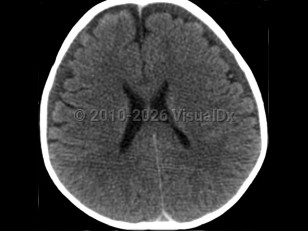

Abusive head trauma, also known as shaken baby syndrome, shaken impact syndrome, inflicted head injury, and whiplash shaken infant syndrome, is a form of trauma that arises when a baby (or small child) is shaken and/or struck so violently that it leads to cerebral injury.

It is thought that the primary injury arises as a result of the multidirectional forces from shaking, leading to a form of whiplash injury associated with diffuse axonal injury, tearing of bridging veins, and subsequent intracranial bleeding. The secondary brain injury is due to a combination of hypoxia, ischemia, and brain edema. The end result is destruction of brain cells, a reduced supply of oxygen to brain cells, and brain swelling leading to varying degrees of neurological deterioration and occasionally death. Anatomically, the combination of a not-yet myelinated brain, a relatively heavy head upon weak neck muscles, and lack of control of the head and neck are factors that predispose babies to this form of injury.

Abusive head trauma may present with one or more of the following clinical features: subdural hemorrhage, retinal hemorrhage, and encephalopathy. Retinal hemorrhages are present in approximately 85% of cases and may be unilateral, but the diagnosis of abusive head trauma should not be excluded if they are absent.